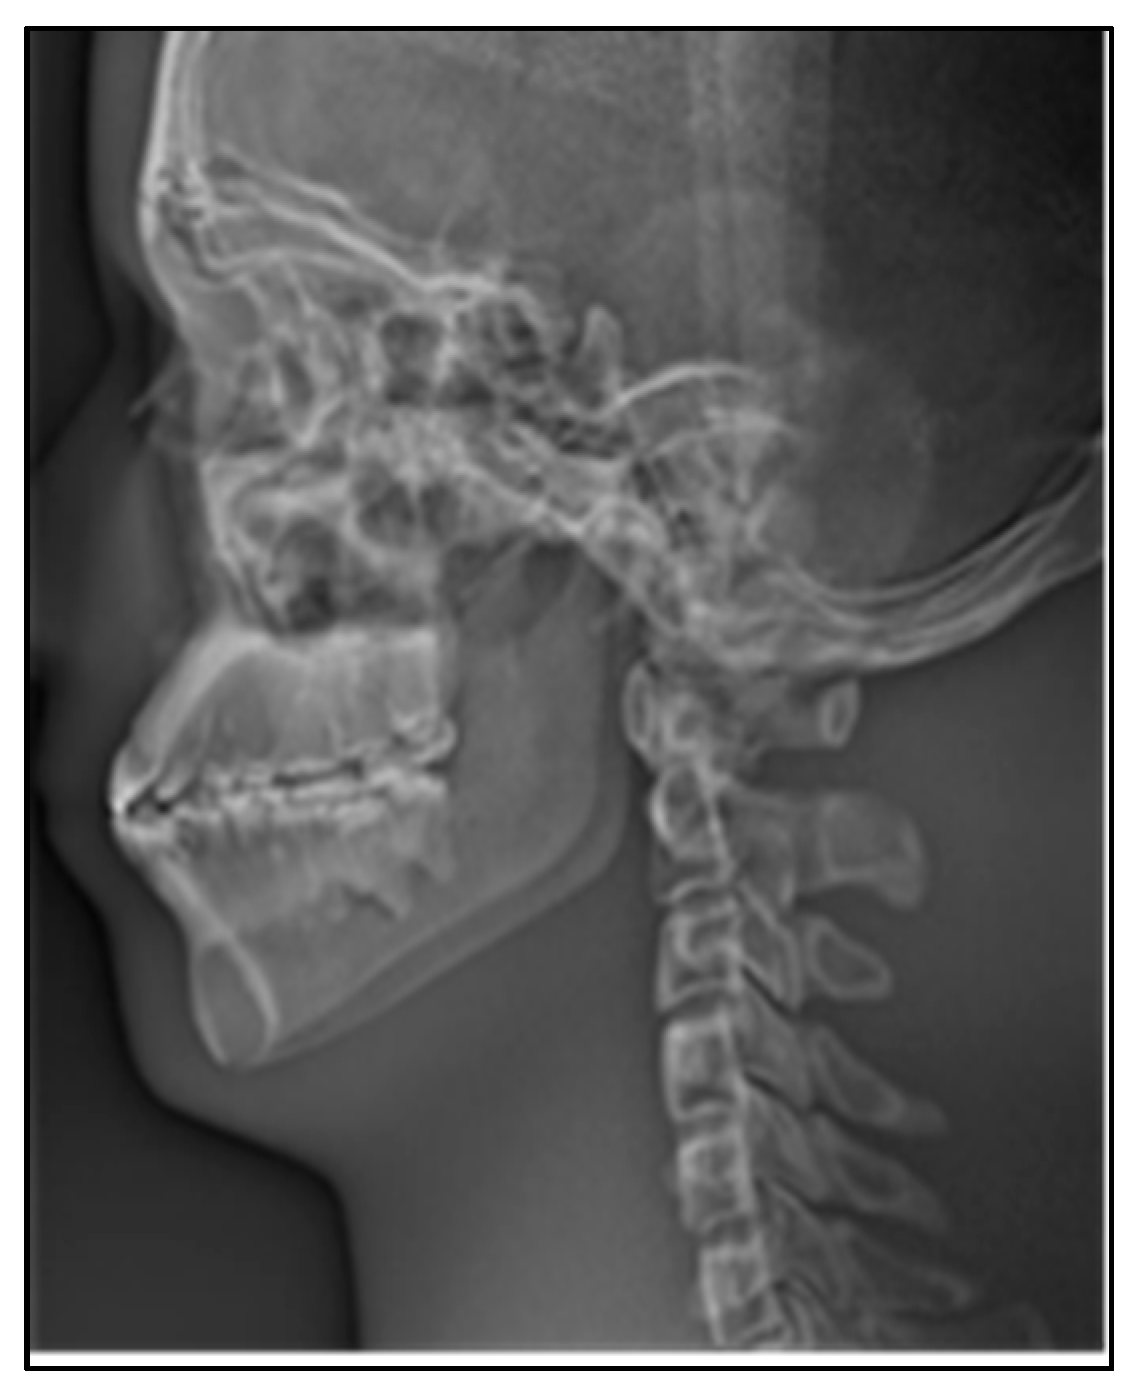

In X-ray imaging, the higher the density of the tissue, the more obvious the absorption of X-rays. In order to make the images more detailed for clinical diagnosis, therefore we need to reverse color manipulation of the stitching panoramic image, as shown in Figure 17.

Figure 17.

Lateral cephalogram after reverse color manipulation.